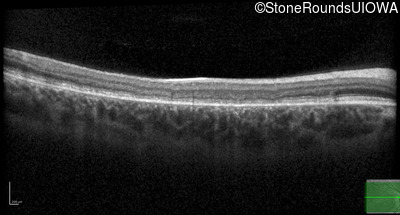

| AR Stargardt Disease | ABCA4 | Asp507Tyr GAT>TAT | IVS40+5 G>A | AR |